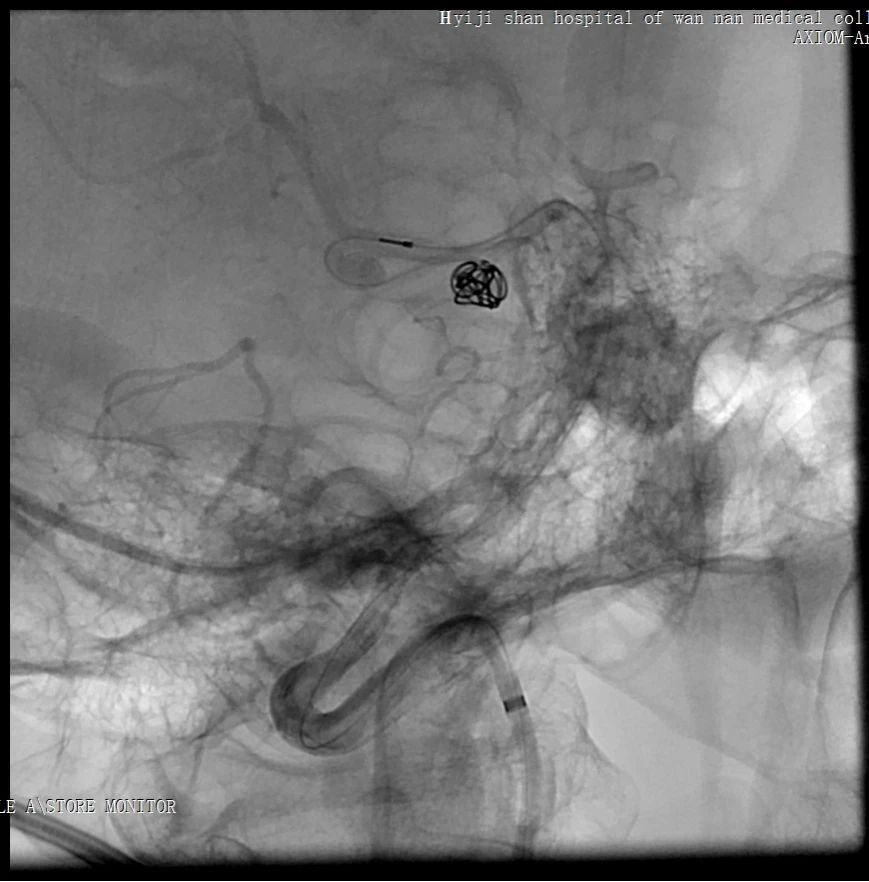

1. 通过椎动脉先将Echelon 10微导管在导丝导引下超选至远端动脉瘤,填塞弹簧圈(Cosmos 4mm/12cm,Jasper 3.5mm/10cm,Axium 3mm/8cm,Jasper 2.5mm/8cm),然后逐渐回撤微导管至近端动脉瘤填塞(Axium Prime 4mm/12cm),最后可见向畸形团供血明显减弱,远端动脉瘤不显影,近端动脉瘤仍有显影。

2. 栓塞大脑中动脉供血的分支血管及畸形团

将Echelon 10微导管超选至右侧大脑中动脉分叉部分支血管远端,微导管造影确认系畸形团供血动脉,DMSO冲管后注射Onyx胶再行造影,可见该分支血管远端闭塞,予以撤出Echelon 10微导管。

用Apollo微导管超选大脑中动脉M1段分支血管直至畸形团内,进行微导管造影确认微导管进入畸形团,DMSO冲管,缓慢注射Onyx 18,路图下可见胶在畸形团内弥散,最后颈内动脉造影可见畸形团完全不显影,但是胶反流导致拔管困难,透视下可见血管移位变形明显。